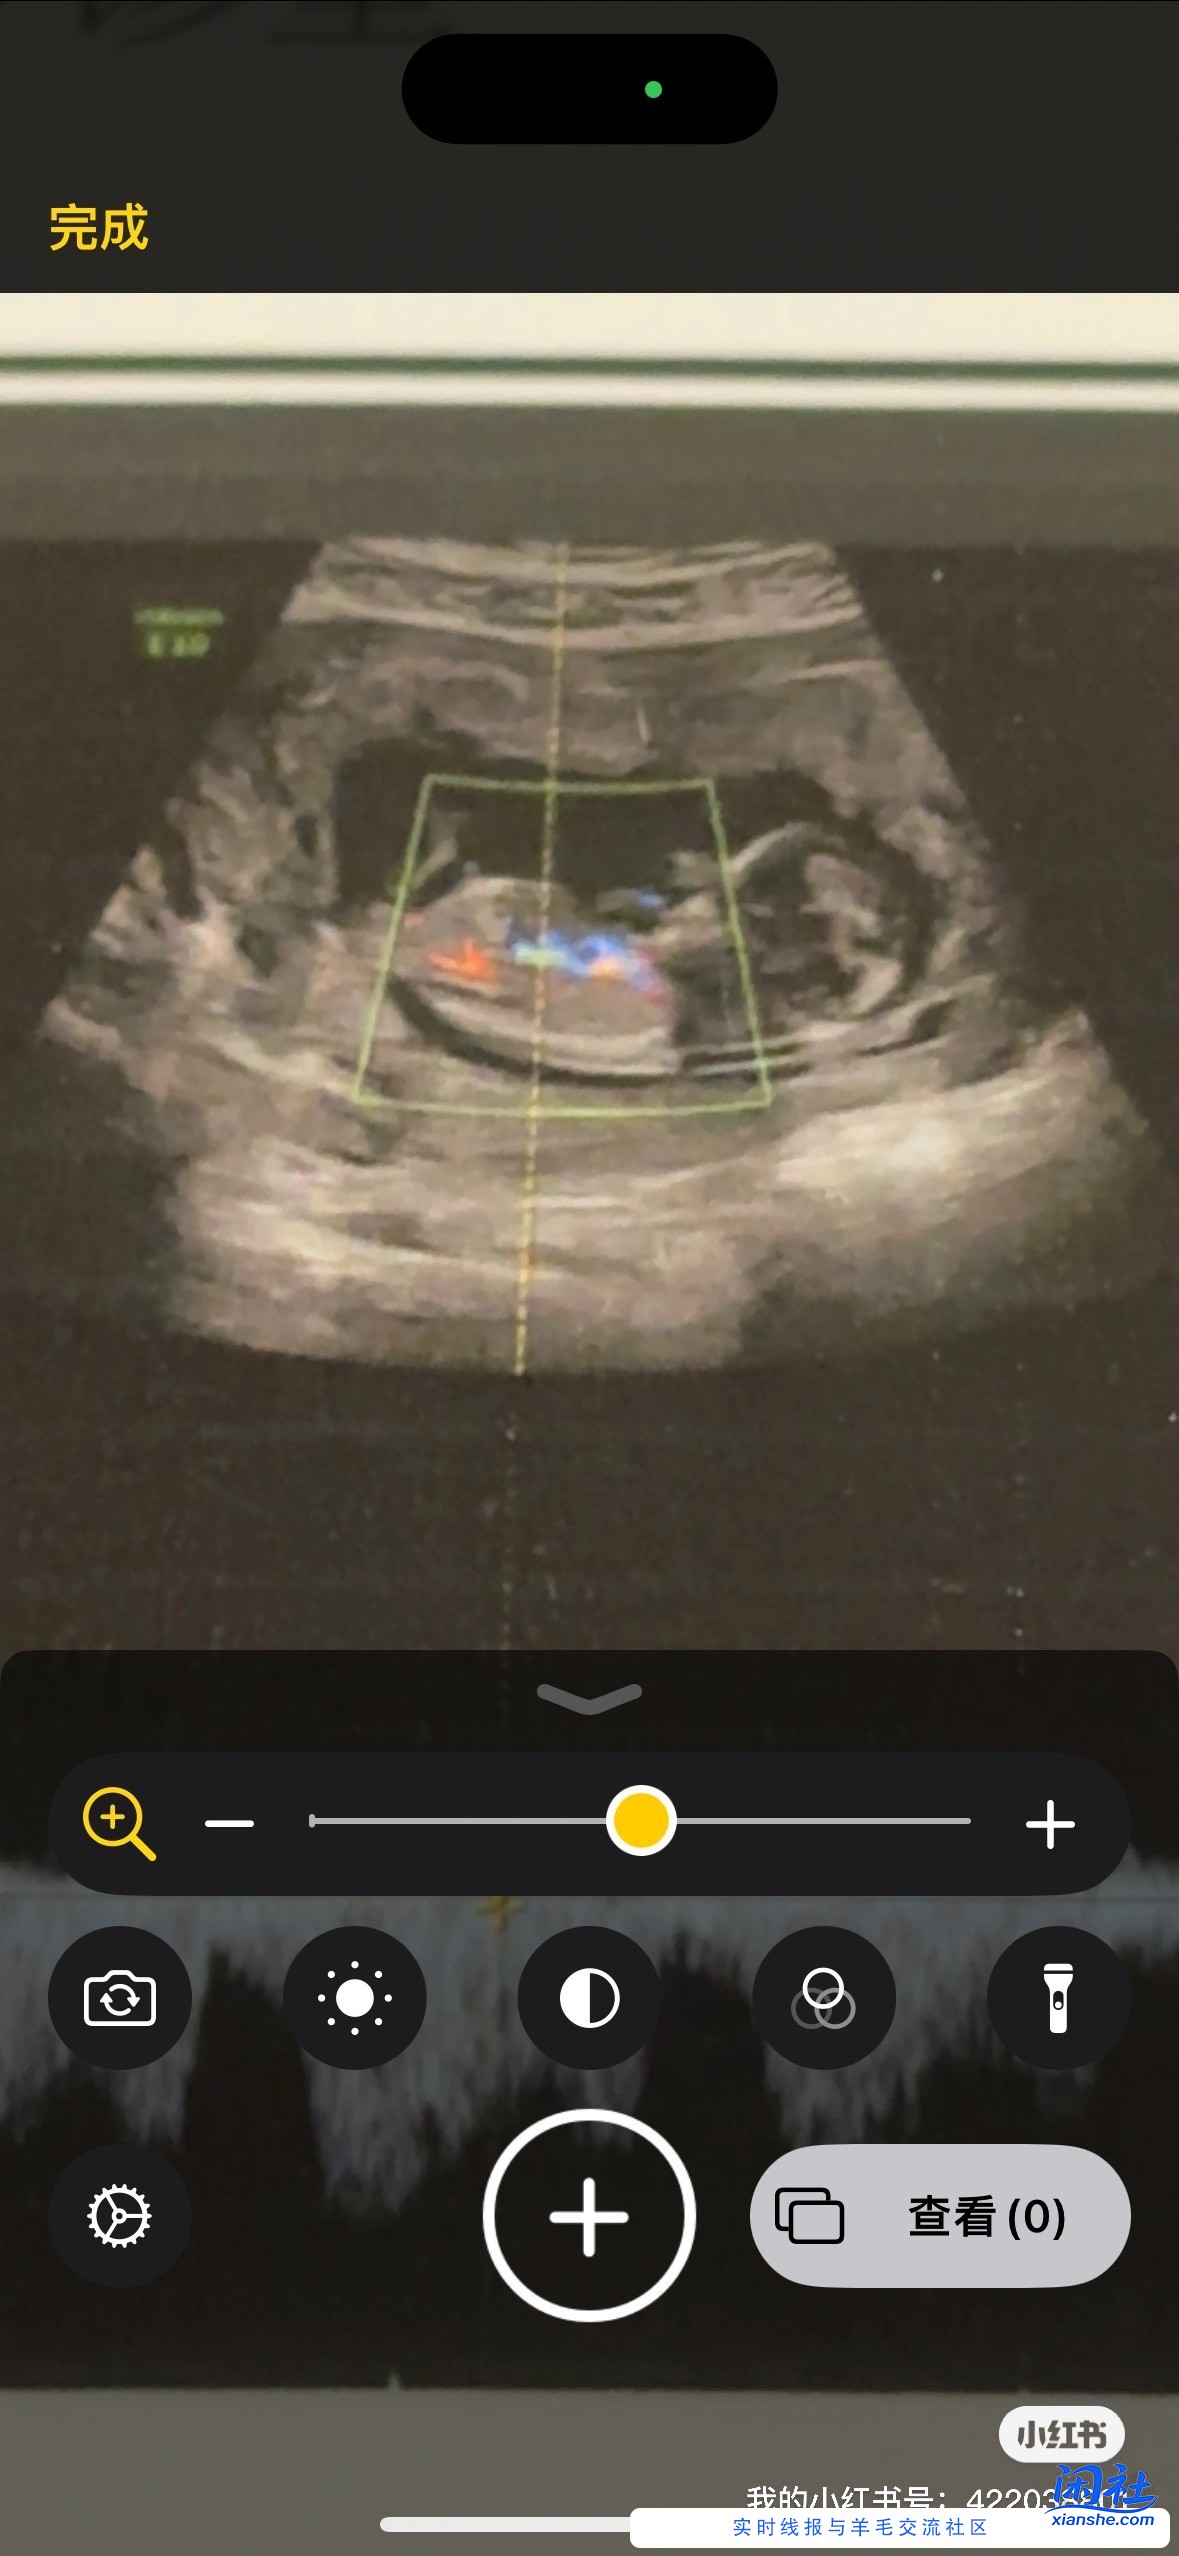

孕12周NT 能看出是蓝宝还是粉宝吗

小姐姐